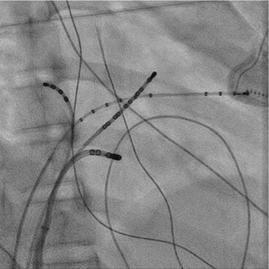

現有VA fusion (圖八),由於可能很靠近coronary artery

擔心用 RF ablation 會造成 coronary artery stenosis or occlusion(2) ,我們在 ablation 前有先做 coronary angiogram (圖九),coronary artery離VA fusion site都有超 過5 mm,所以我們就使用7F non-irrigated RF catheter在 MCV VA fusion site進行ablation,但是沒有效果,接著 我們做了 CS venogram 發現有一個 CS diverticulum 在 MCV (圖十)(3),我們就把電燒導管移到diverticulum的 neck ( 圖十一 ) ,可以看到 VA fusion ,在 RV pacing 下 50W/50oC 電燒一開始 0.7 秒就 VA block ( 圖十二 ) ,接著 RF booster 120 seconds,post-ablation EP study只有看到 在 V pacing 時有 one fast-slow echo beat , antegrade conduction 有 dual AVNs ,但無法誘發任何 AVNRT or AVRT。病患接受完電燒後,沒有再有心悸的症狀。 (圖一)、發作時12 lead ECG (圖二)、12 lead ECG after adenosine use

)、冠狀動脈攝影

(圖九 (圖十一)、X光透視成功電燒的位置在diverticulum neck及3D圖上的成功位置 (圖十二 (圖十 CS diverticulum